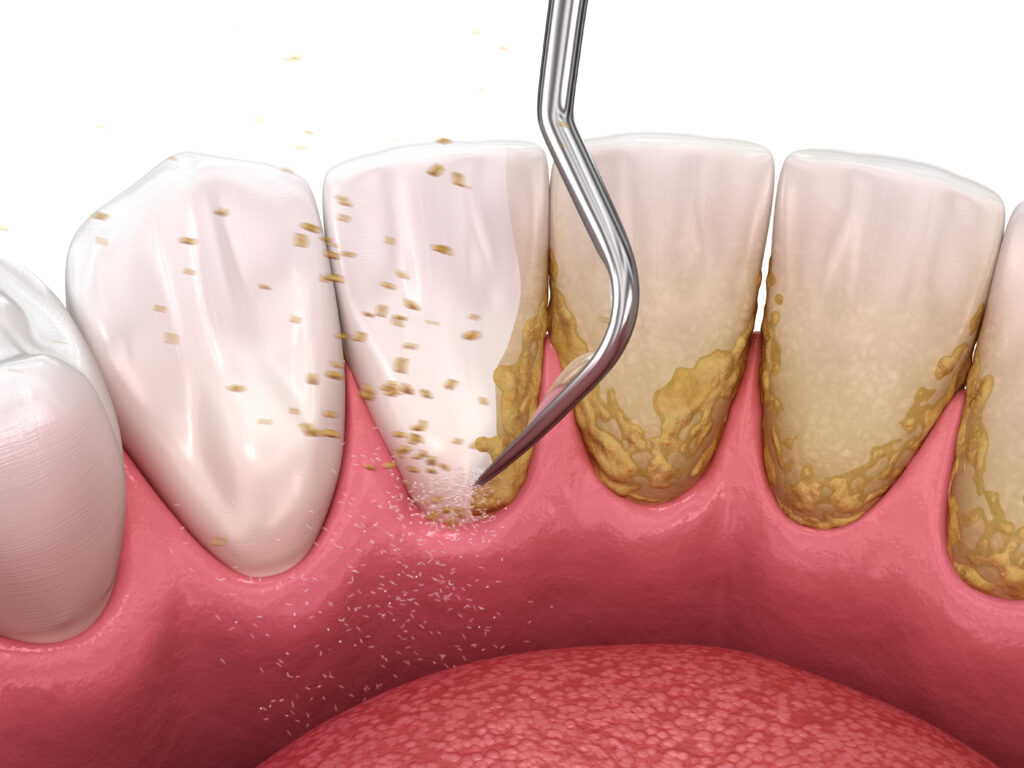

Hambakivi ennetamine

Selles artiklis leiate teavet hambakivi tekke ennetamise kohta. Tekst selgitab hambakivi ennetamise olulisust, annab teavet meetmete kohta, mis vähendavad katulekke teket ning räägib

Professionaalne hambapuhastus – täiusliku naeratuse võti!

Iga inimese suuõõnes leidub üle 200 miljardi mikroorganismi. Ebapiisava või ebakvaliteetse hügieeni tulemusena hakkavad mõned neist põhjustama hambakivi moodustumist. Hambaid ründavad patogeensed mikroorganismid tekitavad ebameeldiva lõhna, muudavad hamba kollaseks ja aktiveerivad isegi põletikulisi protsesse.